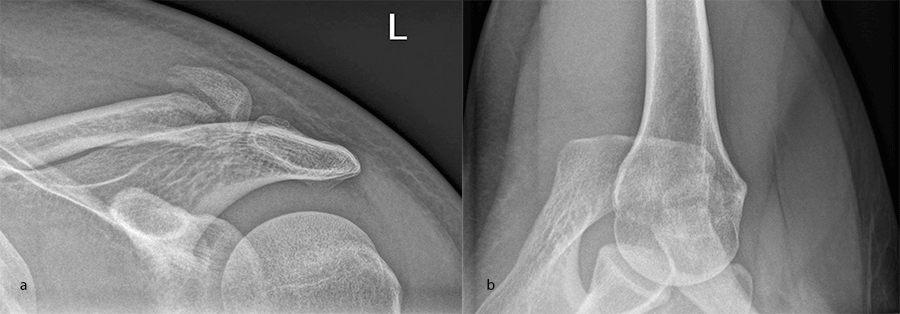

Case 1: lateral plate

A 30-year-old man sustained a lateral fracture to his left clavicle following a fall from his bike (Fig 9). Intraoperative images indicate plate placement and screw insertion (Fig 10). Intraoperative image revealing usage of sutures through the plate for soft- tissue fixation (Fig 11). Image shows the fracture healing at 8 weeks' follow-up (Fig 12).